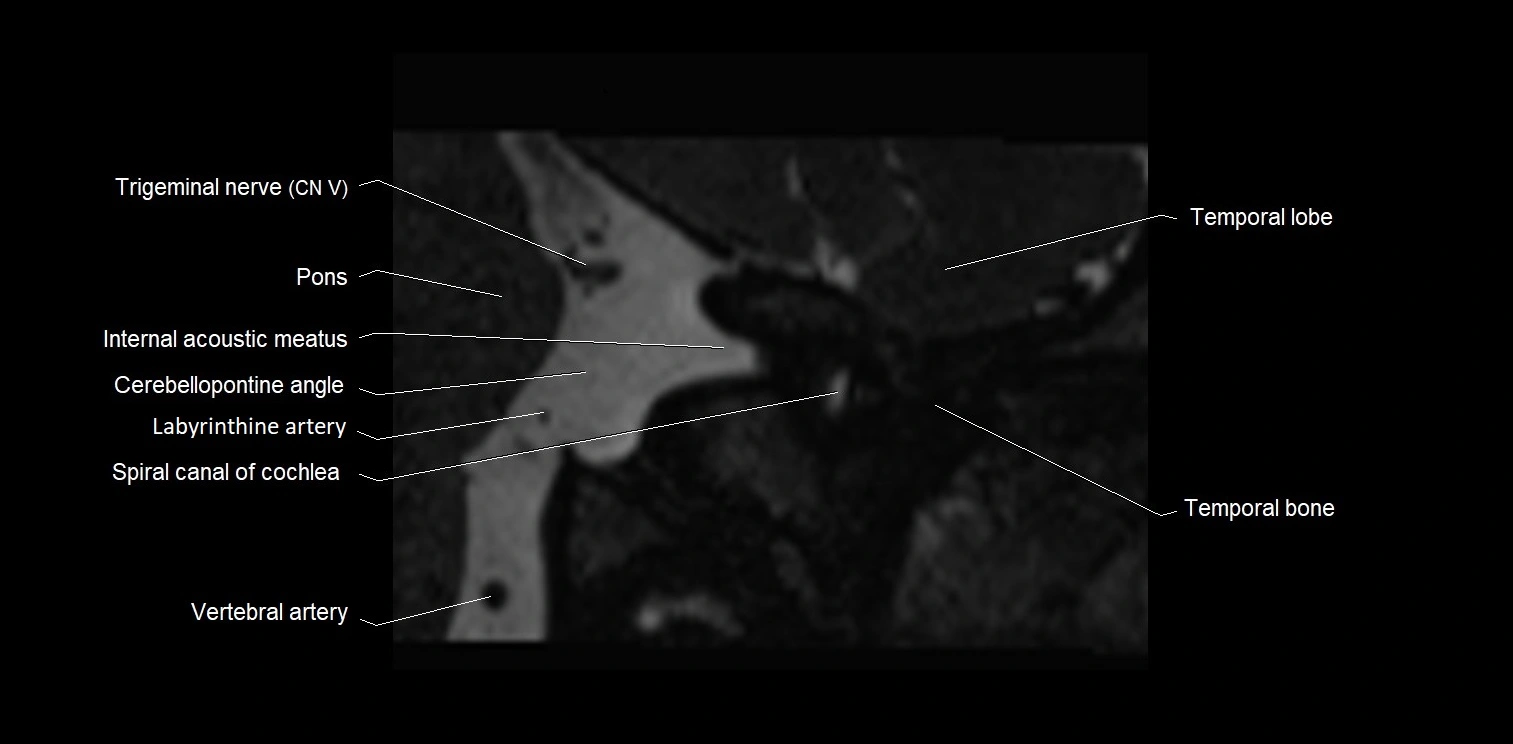

MRI Appearance

• The abducens nerve is a small, thin, linear structure

• Best visualized on high-resolution T2-weighted 3D MRI sequences (e.g., FIESTA or CISS)

• Seen as a hypointense (dark) line running from the brainstem at the pontomedullary junction, traversing the prepontine cistern, and entering Dorello’s canal under the petrosphenoidal ligament, then into the cavernous sinus, and finally the orbit

• May be challenging to visualize in standard MRI due to its small size

• Pathology may be inferred by absence, displacement, or enhancement of the nerve

MRI images

image